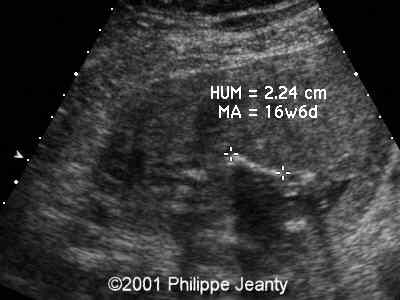

Durante la gravidanza, le donne possono essere sottoposte a screening mediante prelievo di villi coriali (villocentesi) e amniocentesi per rilevare la trisomia 16. Con l'avvento delle tecniche non invasive per la rilevazione dell'aneuploidia, lo screening prenatale con test che utilizzano il sequenziamento di nuova generazione può essere utilizzato prima delle tecniche invasive. Ciò può causare un ritardo della crescita fetale.